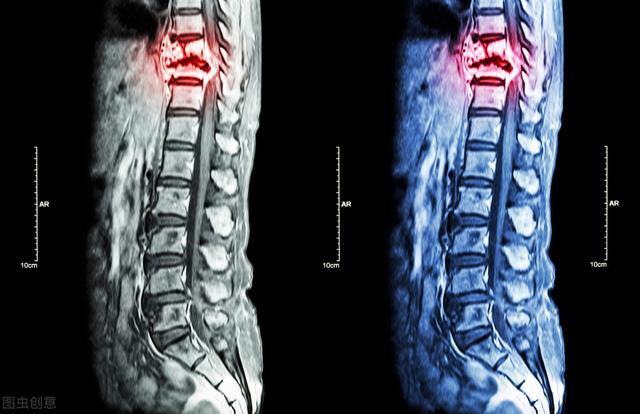

Imagerie par résonance magnétique des métastases osseuses

Montrant un cancer avec métastases osseuses survenant dans la colonne vertébrale thoracique